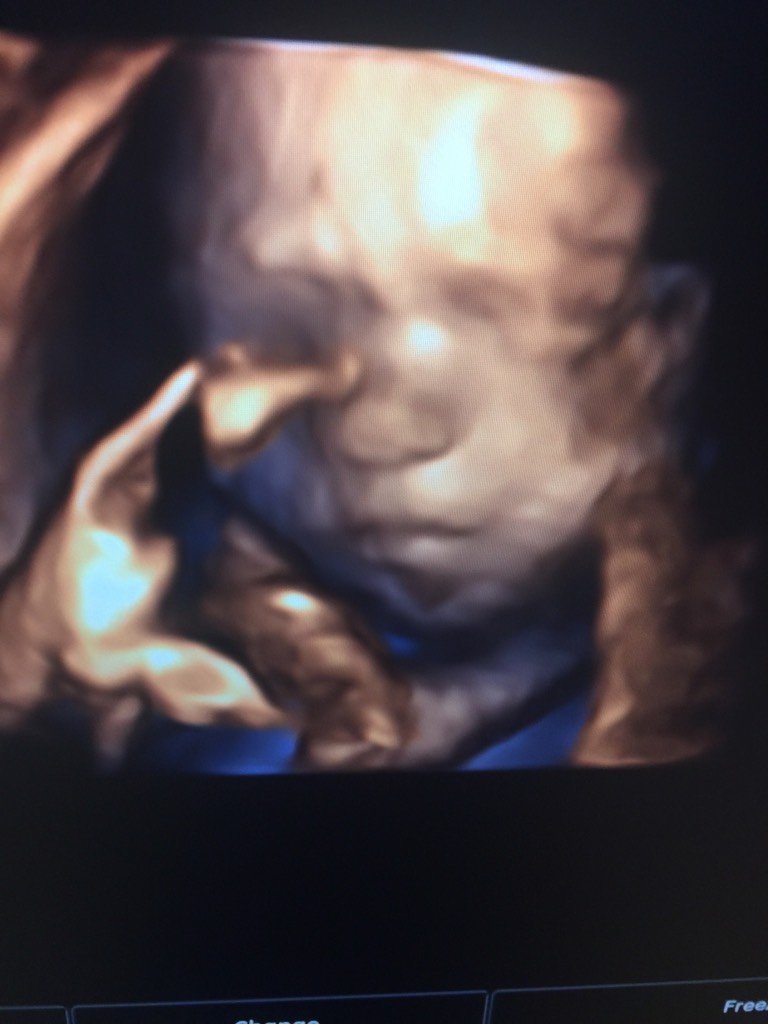

四维照片可以看出男女吗?大家来看看像男孩女孩,娱乐一下 四维照片可以看出男女吗?大家来看看像男孩女孩,娱乐一下。 点击展开 茉莉蜜茶158 2015-07-01 21:27 为您推荐: 其他回答 像男孩,, 我爱大小宝 2015-07-01 22:02 男宝宝。双顶颈股骨发下就清楚了。 旺旺家常菜 2015-07-01 22:01 一般通过四维彩超做排畸检查时是可以检测出胎儿生殖器官的,但是通过照片是无法判断的 cn#BappGGkLQQ 2015-07-01 21:54 看不出,,,, 150*****254_ffTW 2015-07-01 21:45 男孩。。。。 乖zhi死不离 2015-07-01 21:44 加载更多 相关问题 看四维上宝宝的照片能看出男孩女孩吗? 37+4了,终于快和宝宝见面了,宝妈们都来娱乐一下男孩女孩,,,好期待呀 娱乐娱乐,嘿嘿,帮我看看我家宝宝是男孩女孩啊,听人家说双顶径减去股骨长大于二就是男宝,我的是二十五